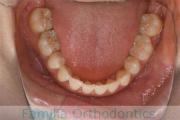

左下の奥歯が内側に倒れているのを治したいということで来院されました。かみ合わせが深い、上顎前突(出っ歯)の患者さんでした。上下左右から小臼歯を抜歯して、大臼歯を起こしながら治療を行いました。約3年、35回程度の通院をしていただきました。

かみ合わせが深いため、治療を行わないと前歯の裏側の歯茎を咬んでしまうリスクがありました。

- ≫治療後

上顎

下顎

前歯の関係など

右側

正面

左側